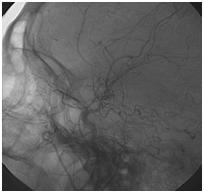

Mujer de 46 años que ingreso por cefalea súbita, hemiparesia izquierda y disartria, con tomografía axial computarizada cerebral simple que mostró hemorragia frontoparietal derecha drenada a ventrículos y arteriografía con patrón Moyamoya. Reingreso 3 meses después con deterioro del estado de consciencia y tomografía axial computarizada cerebral simple que mostró hemorragia intraparenquimatosa temporoparietal izquierda con extensión intraventricular y desviación de la línea media, se manejo en Unidad de Cuidados Intensivos con traqueostomía y gastrostomía, presentó neumonía y sepsis nosocomial, finalmente falleció en la Unidad de Cuidados Intensivos.